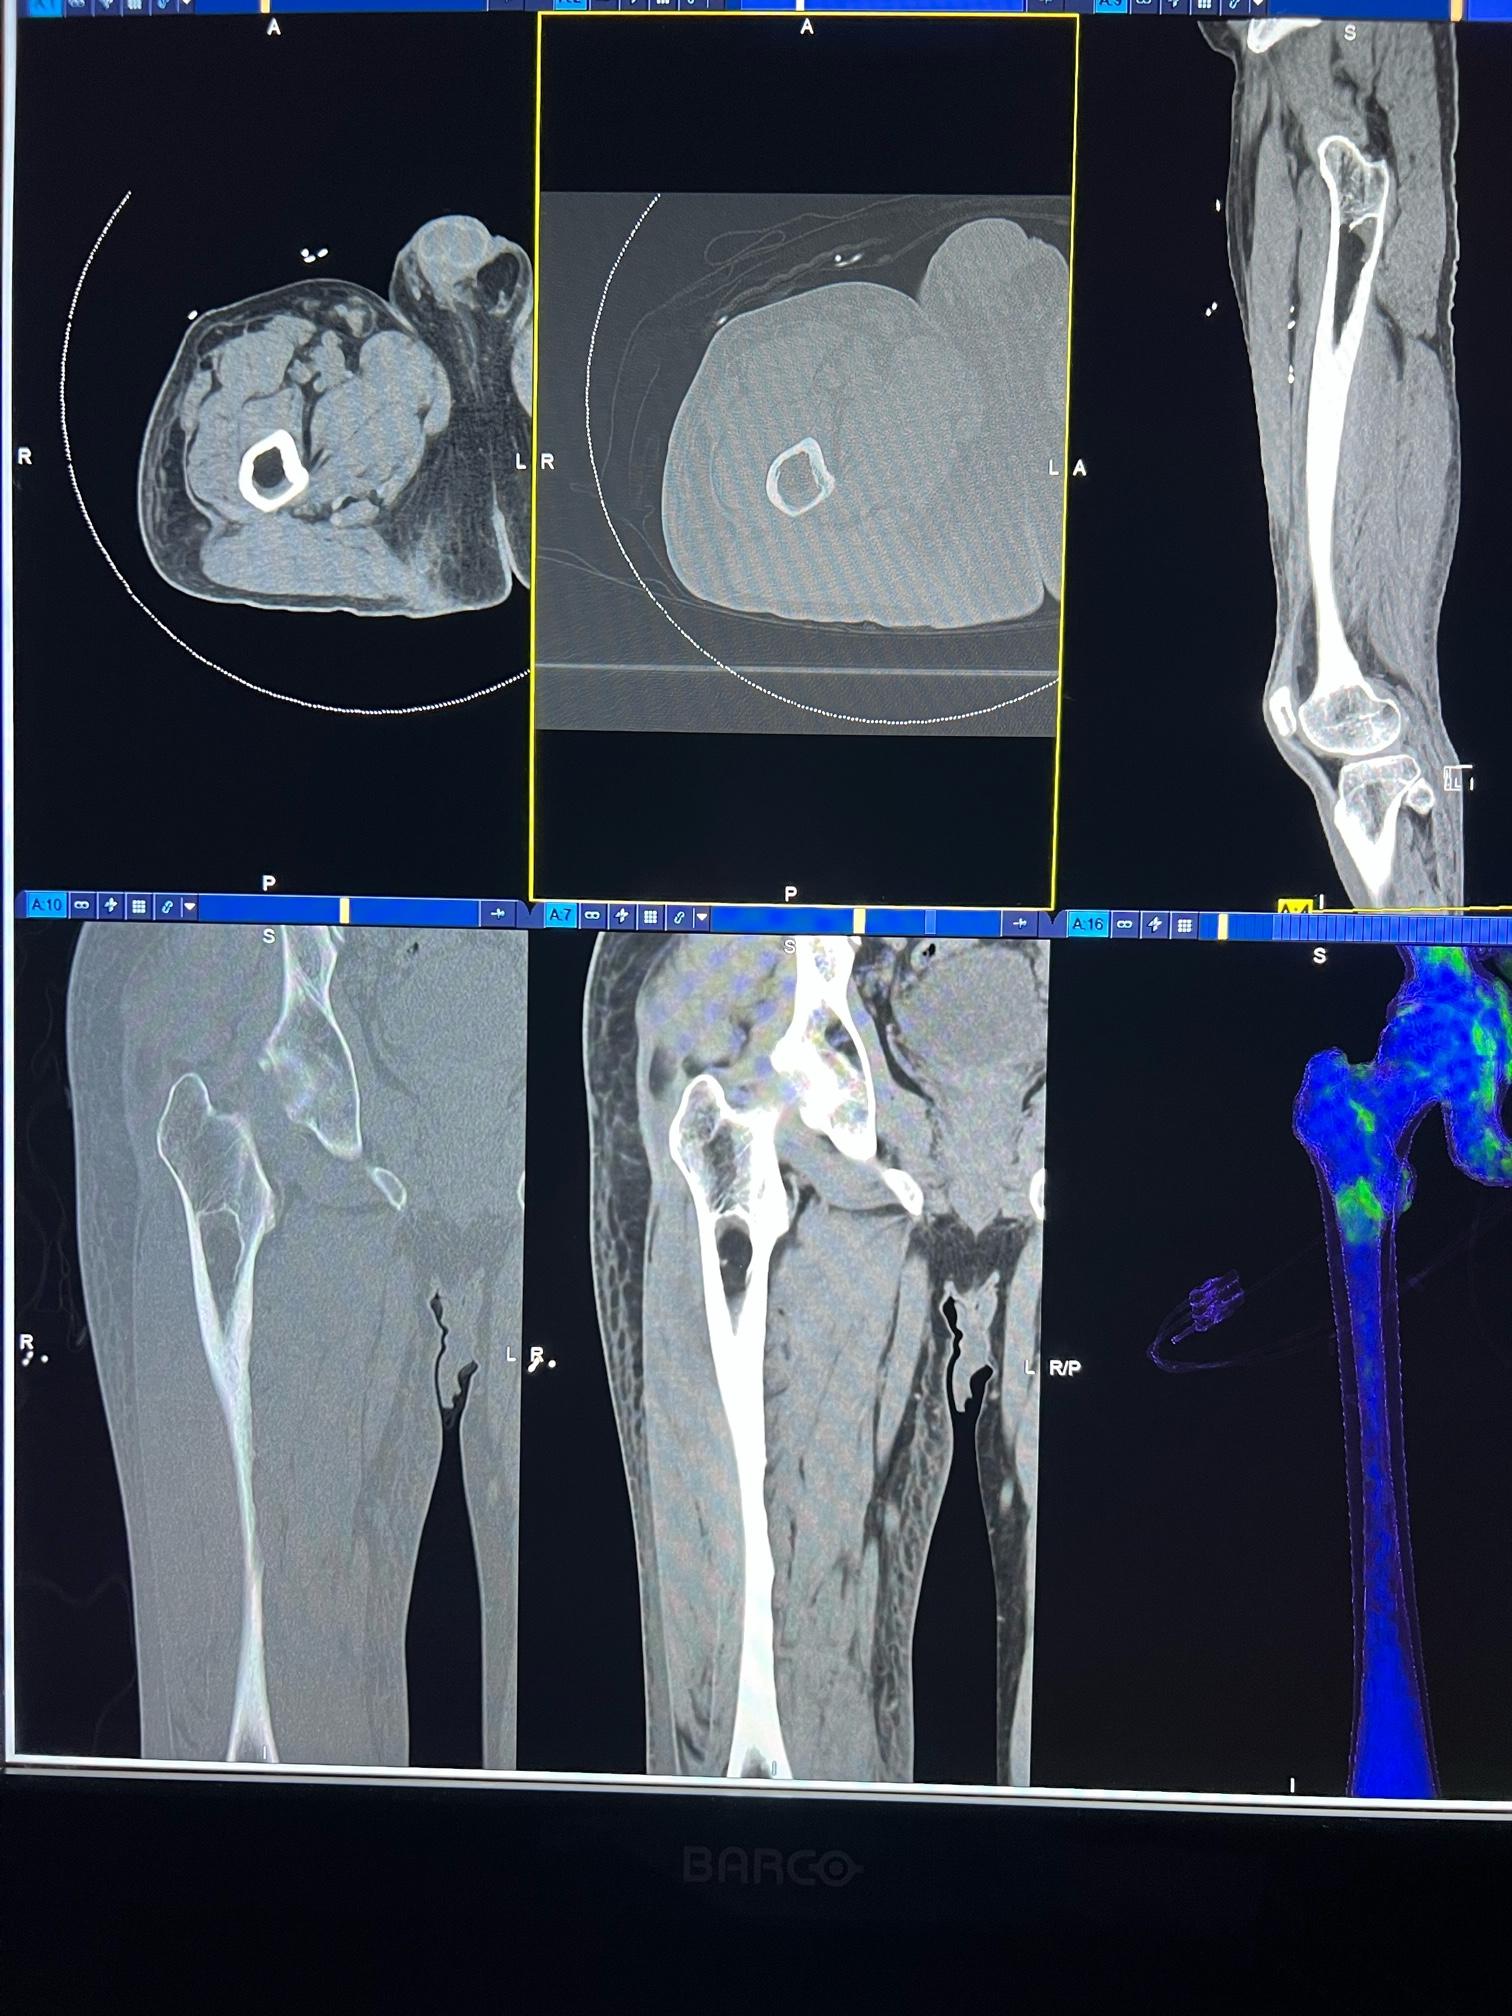

image1